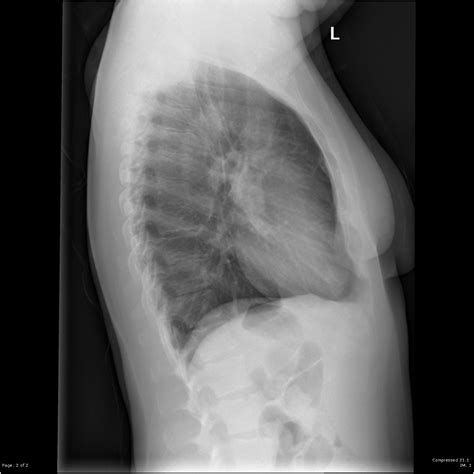

Interpreting a Normal Lateral Cxr

Interpreting a Normal Lateral Cxr requires a trained eye and a deep understanding of anatomy. Radiologists look for various indicators to assess the health of the chest cavity. Some key elements to consider include:

• Lung Fields: The lungs should appear clear, with no signs of consolidation, masses, or fluid. Any opacities or abnormalities can indicate infections, tumors, or other conditions.

• Heart Size and Shape: The heart should be of normal size and shape. An enlarged heart (cardiomegaly) can indicate conditions like heart failure or hypertension.

• Diaphragm: The diaphragm should be clearly visible and in its normal position. Elevation or flattening of the diaphragm can indicate underlying issues.

• Bones and Soft Tissues: The ribs, spine, and soft tissues should be examined for any fractures, dislocations, or masses.

• Mediastinum: The mediastinum, the central compartment of the thoracic cavity, should be assessed for any widening or abnormalities, which can indicate conditions like lymphadenopathy or aortic aneurysms.